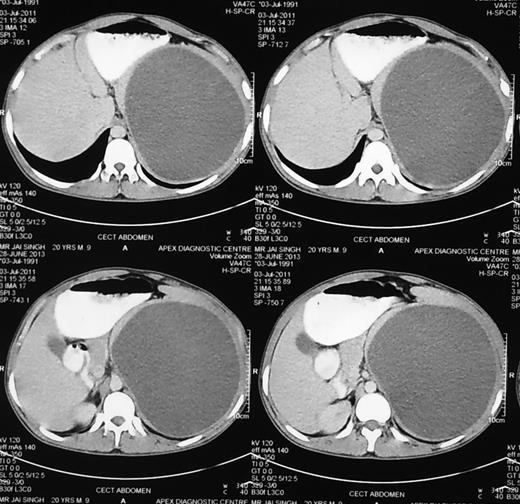

A 47-year-old female presented with complaints of a small lump (Figs 1–5) in left upper abdomen and a past history of fall on ladders a year back. On examination, there was a small lump confined to the left hypochondrium, firm in consistency with rounded borders suggesting origin from the spleen. The patient underwent CT scan of the abdomen after abdomen sonography and CECT suggested the presence of a cystic lesion originating from the lower margin of spleen ∼12 × 8 cm in size. The patient underwent a surgery and cystic lesion was removed preserving the spleen (Figs 6–8). The cyst on histopathological examination was a pseudocyst.

CECT abdomen showing huge splenic mass compressing surrounding structures.